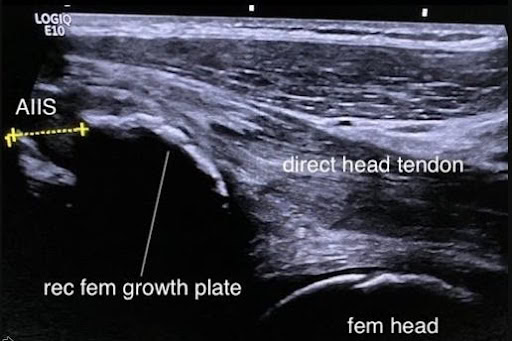

The mechanism of injury involved a forceful football kick, placing rectus femoris under high load, leading to avulsion of AIIS (figures 10 and 11).

Figure 11- Ultrasound AIIS

Progressive heterotopic calcification of the displaced apophysis and scar (subsequently demonstrated on CT scan), led to subspinous hip impingement and marked loss of sporting function and range of movement.